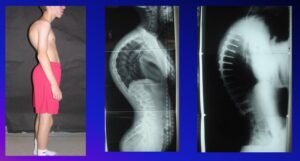

Most common causes of Kyphosis in children include Scheuremann’s disease, Congenital malformation and neuromuscular disease. Typical characteristic findings in Scheuremann Kyphosis include irregular endplates, vertebral wedging and Schmorl’s nodes. Congenital Kyphosis usually result from defects of formation with resultant posterior hemivertebra and segmentation defects with anterior bar. Neuromuscular Kyphosis in children result from muscular imbalance due to a myopathic condition or neurologic dysfunction with asymmetric paralysis or weakness

Surgical indications in Scheuremann’s Kyphosis include kyphosis greater than 75° in adolescents and adults, pain, deformity unresponsive to brace and Cosmesis. Most cases can be adequately treated with current posterior segmental instrumentation such as pedicle screws and obviate the need for anterior releases in order to reduce postoperative morbidity. A recent study comparing Kyphosis correction by anterior versus posterior only pedicle screw approach showed that, posterior only conserved and maintained better kyphosis correction than with combined fusion; with less complications.